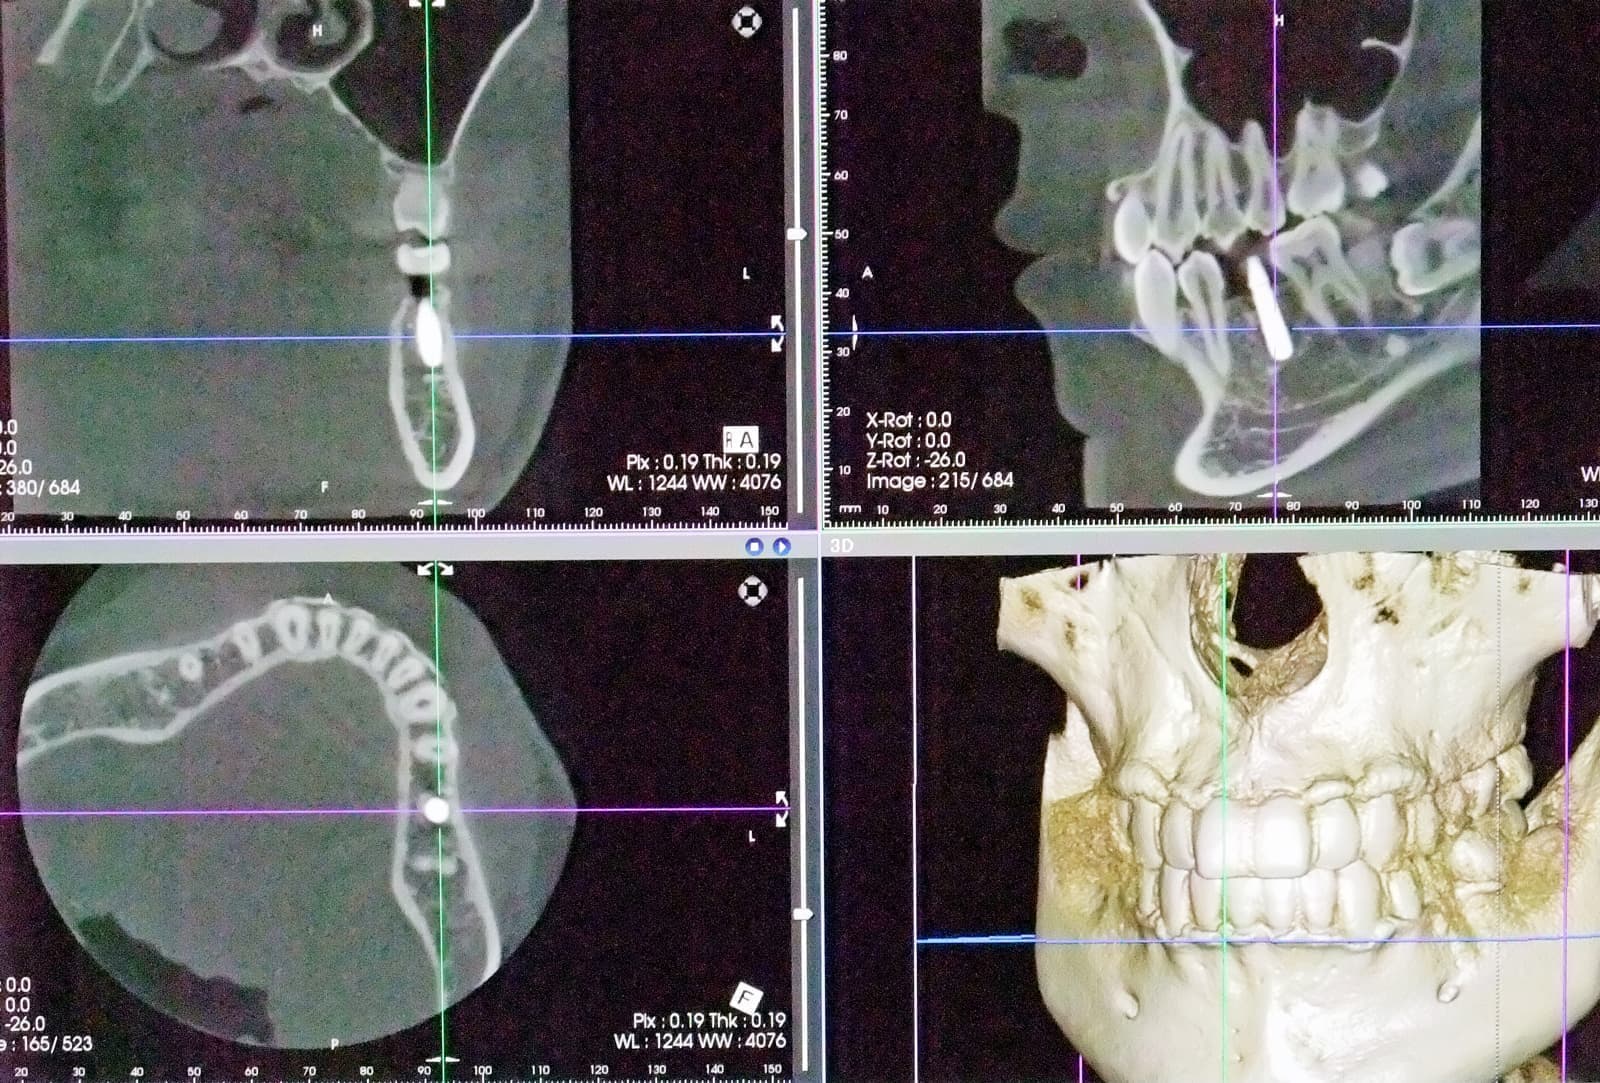

CT 3D デジタルレントゲン

HCT 3D Roentgen

高精細で被爆量も少なく安心

当院では、歯科用CT3Dデジタルレントゲンを活用し、身体への負担を少なく、状況を詳しく把握し、的確な治療を提供出来るよう心掛けております。

CTデジタルレントゲンに使われているX線センサーは高感度で照射時間も短く、より低線量でのレントゲン画像の取得が可能となり、お子様にも安心です。

インプラント手術や歯周病治療、歯列矯正治療、歯の根の病気に関係する治療の正確な診断、治療計画には、3DCTによる撮影が欠かせません。

例えば、親知らずの抜歯や骨内に埋伏している過剰歯の抜歯等、正確な位置や神経や血管等との距離を3次元的に把握することで負担の少ない安心な処置が行えます。